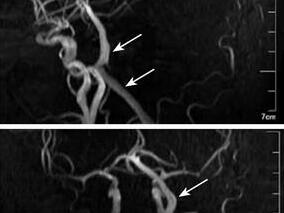

两个锁骨下动脉近心段狭窄但无经椎动脉自颅内“盗血…

1小时条评论1 病例简介 例1,患者男,60岁。主因头晕不适伴左上肢无力1周于2009年12月15日于本院神经内科就诊。患者于就诊前1周日常活动中出现头晕不适,无意中发现左上肢无力,休息数小时后头晕症状有所缓解,但仍感左上肢轻微无力。初次发作后未予重视,未立即到医院就诊,...